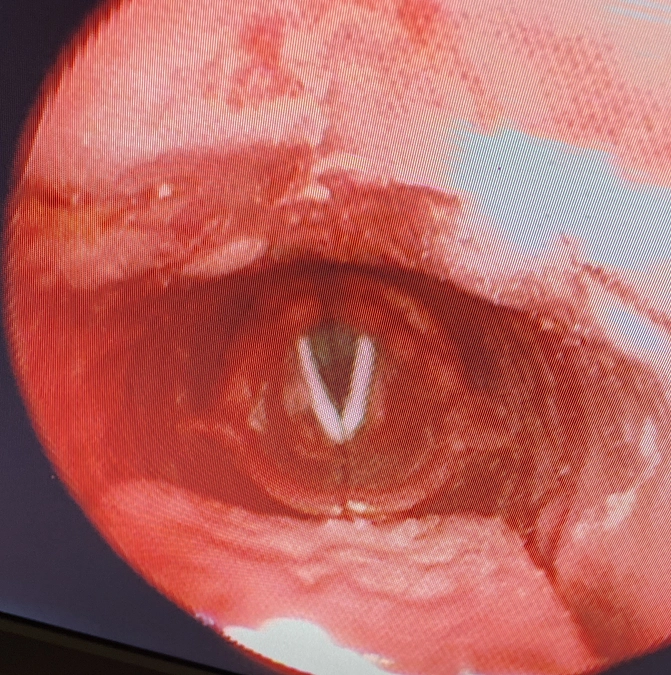

嚥下内視鏡ケーススタディ用のマネキン作製進捗について

今週ようやく、1体目を組み立てる段階まできました。

元のモデルとの違いですが、元のモデルが歯科用のアクリルレジンと

市販のホビー用のレジンで手探りで作製したものでした。

これを基に分解したモデルの3Dデータ化をおこない、

3Dプリンターで複製し組み立てたものが、今回の1体目のマネキンになります。

元のモデルはレジンの塊でたいへんな重量(2kg程度)がありました。

3Dプリンターで作製したモデルは、非常に軽く(500mg程度)扱いやすくなりました。

しかしながら、複製した各パーツについては細かい調整をしなければ

形にすることがまだまだ難しく、円滑な量産体制には至っていません。

今後、データ上の細かい調整作業を繰り返し、容易に量産できるようになりましたら、

これからVEを実践される仲間にマネキンを届けて、多くの嚥下障害の患者さんに

応えられる機会がつくられるきっかけになればと思います。